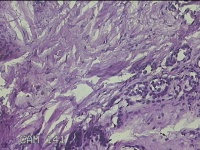

左面部赘生物

性别

男

年龄

47岁

临床诊断

纤维瘤;皮肤感染

一般病史

面部皮肤起赘生物8年。

标本名称

大体所见

灰白粉红色肿物1.3x1.2x0.3cm一个,表面光滑,肿物表面有少许毛发,切面灰白粉红色,质软。

复合痣?